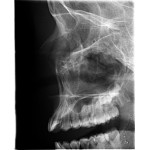

Programa ATM doble lateral PA

El programa doble ATM produce vistas laterales y posteroanteriores de las articulaciones temporomandibulares cerradas y abiertas en una sola radiografía. La imagen radiográfi ca, obtenida por este proceso, permite un fácil diagnóstico de las condiciones de las ATM de un vistazo.